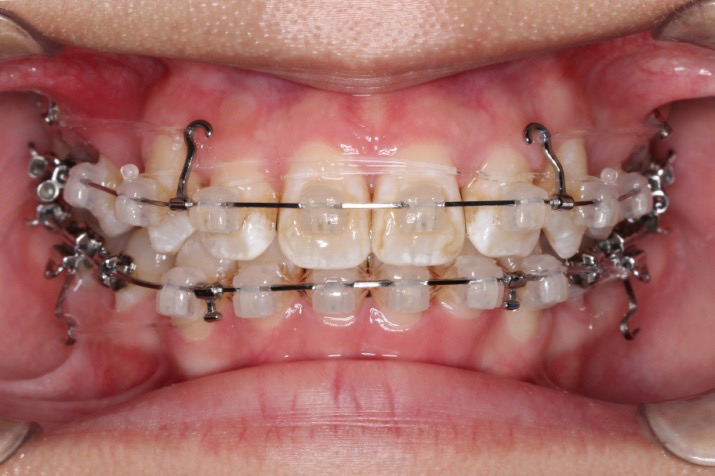

2018.11.14  术后侧面改善明显,露龈笑改善明显,笑弧笑线协调,颏部肌肉紧张度明显改善

2018.11.14  术后磨牙尖牙I类关系,中线齐,覆合,覆盖正常

宏观评价:面部对称,面下三分一比例协调,上下唇凸度正常,上颌牙列内收转矩控制良好,下颌后缩改善,颏唇沟变得更加柔和,术后达到基本直面型。

迷你观评价:上下牙齿中线与面中线对齐,笑弧协调,微笑时牙龈暴露量正常,微笑时横向正常,左右唇基本对称。

微观评价:牙齿整齐,咬合关系良好,上下前牙转矩及突度控制良好,磨牙关系I类,尖窝咬合关系良好,OB,OJ正常。